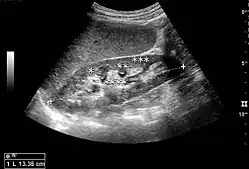

The kidney is divided into parenchyma and renal sinus. The renal sinus is hyperechoic and is composed of calyces, the renal pelvis, fat and the major intrarenal vessels. In the normal kidney, the urinary collecting system in the renal sinus is not visible, but it creates a heteroechoic appearance with the interposed fat and vessels. The parenchyma is more hypoechoic and homogenous and is divided into the outermost cortex and the innermost and slightly less echogenic medullary pyramids. Between the pyramids are the cortical infoldings, called columns of Bertin (Figure 1). In the pediatric patient, it is easier to differentiate the hypoechoic medullar pyramids from the more echogenic peripheral zone of the cortex in the parenchyma rim, as well as the columns of Bertin (Figure 2).[1]

Figure 2. Normal pediatric kidney. * Column of Bertin; ** pyramid; *** cortex; **** sinus.[1]